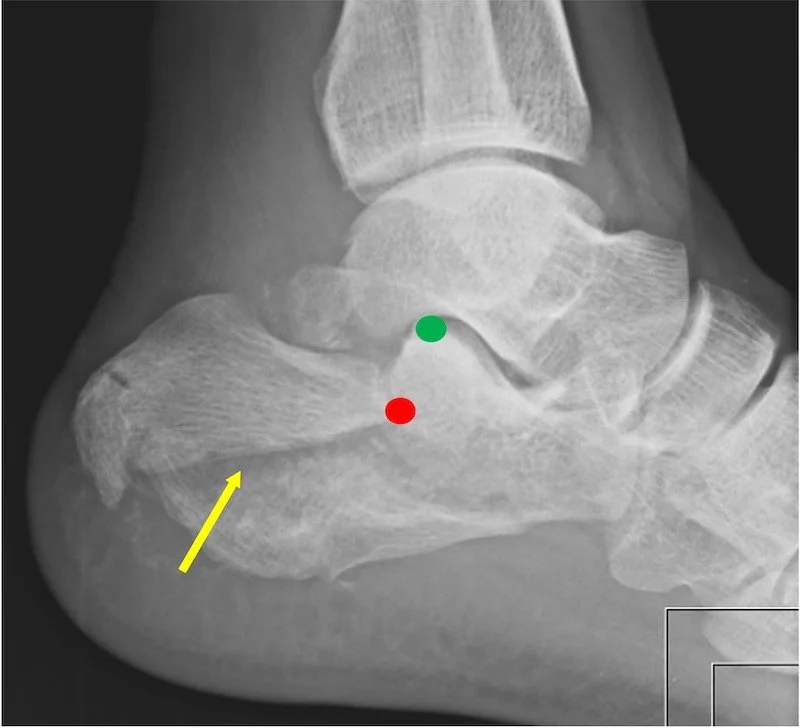

We generally divide the fractures into two categories, above we showed a joint depression fracture, here below is the tongue type fracture. It is called that because the fracture fragment “looks like a tongue”. The pattern is different because the position of the foot was different when the body weight came down into the foot. The red dot shows the front edge of the tongue fracture and that red dot should actually be where the green dot is. The yellow arrow points to the fracture line which is easy to see in this case. The next xray shows only the green dot because we repaired the fracture and realigned it. You cn see the surgical plate holding the bone together.